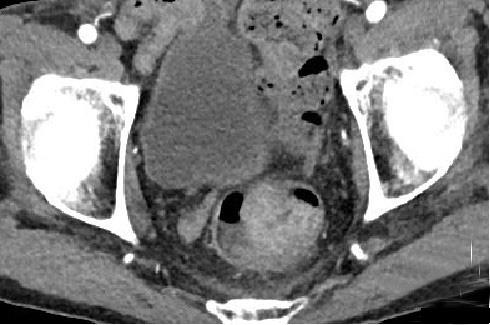

• 计算机体层摄影血管造影在腹腔镜结肠癌根治术前评估中的应用效果

2025, 31(6):24-31. DOI: 10.12235/E20240177

摘要 (181) HTML (147) PDF 4.65 M (171) 评论 (0) 收藏

摘要:目的 分析计算机体层摄影血管造影(CTA)在腹腔镜结肠癌根治术前评估中的应用效果。方法 回顾性分析2021年1月-2024年2月于该院接受腹腔镜结肠癌根治术的120例患者的临床资料。其中,60例行常规腹部CT和CTA,60例行磁共振成像(MRI)。以术后病理为金标准,判断CTA对临床T分期与术后病理的一致性,以及评估肿瘤是否侵犯肠系膜血管和周围组织的准确度。结果 术前CTA诊断T分期的准确率为95.00%(57/60),一致性好(Kappa = 0.925,P < 0.05);术前MRI诊断结肠癌T分期的准确率为98.33%(59/60),两者比较,差异无统计学意义(χ2 = 0.26,P > 0.05)。CTA预判肿瘤是否累及肠系膜上动脉、肠系膜上静脉、肠系膜下动脉、肠系膜下静脉、腹主动脉、肾动脉、肾静脉和脾动脉等血管,与术后病理的一致性好。特别是在预测肠系膜血管受累方面,CTA的敏感度为94.44%,特异度为95.83%,准确度高达95.00%。结论 对于行腹腔镜结肠癌根治术的患者,术前CTA不仅能清晰地显示结肠癌T分期,还能揭示肠系膜血管的走行和变异,以及肿瘤与周围组织的关系和侵犯程度,从而为手术规划提供强有力的支持,确保了腹腔镜手术的安全性,减少了不必要的手术风险。